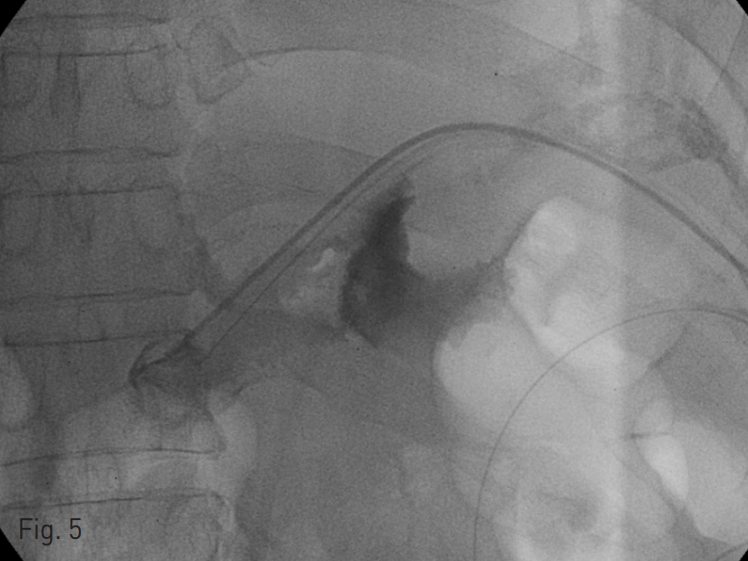

Fig. 5

Contrast material is infused to visualize localized fluid collection through 5 Fr yellow sheath.

Demonstration of localized fluid collection around esophagojejunostomy site and anterior aspect of duodenal stump.

These findings were correlated with CT findings.